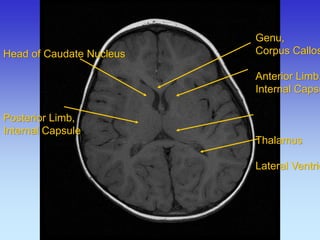

Head of Caudate Nucleus Posterior Limb, Internal Capsule

Genu,

Corpus Callosum

Anterior Limb,

Internal Capsule

Thalamus

Lateral Ventricle

Anterior Limb, Internal Capsule

Head of Caudate Nucleus Third Ventricle Lateral Ventricle